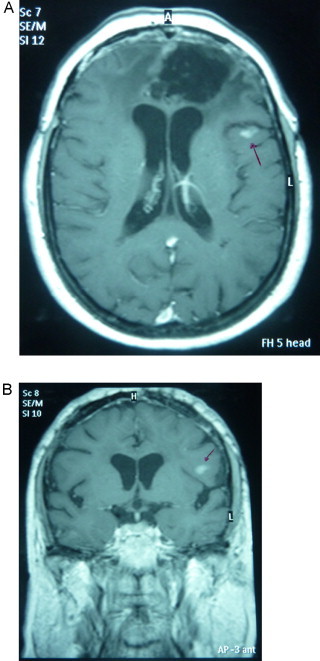

Fig. 2.

A-B IMR axial and coronal view of local recurrence.